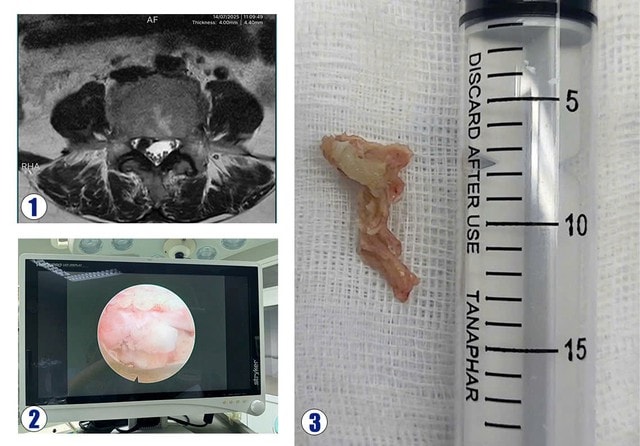

Bệnh nhân Nguyễn Thị S. (53 tuổi, ở xã Nghĩa Đàn – Nghệ An) nhập viện trong tình trạng đau dữ dội chân phải, đi lại khó khăn. Bệnh nhân đã được điều trị nội khoa 2 tuần nhưng không đỡ đau. Kết quả chụp MRI cột sống thắt lưng phát hiện khối thoát vị đĩa đệm L4L5 chèn ép rễ L5 bên phải.

Bệnh nhân được chỉ định phẫu thuật nội soi lấy khối thoát vị đĩa đệm. Ca phẫu thuật kéo dài gần một tiếng, khối thoát vị đã được lấy qua nội soi, rễ L5 phải được giải phóng chèn ép. Sau phẫu thuật, bệnh nhân hết đau hoàn toàn chân phải, vận động tốt và trở lại sinh hoạt thường ngày chỉ sau một ngày.